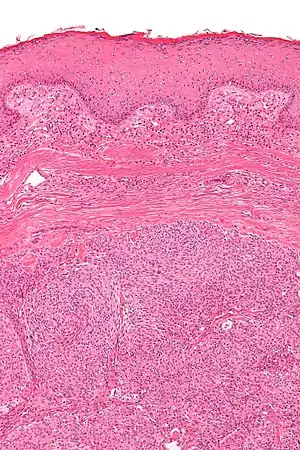

| Micrograph showing an acrospiroma. H&E stain. | |

Discussion of sweat gland tumors can be difficult and confusing due to the complex classification and redundant terminology used to describe the same tumors. For example, acrospiroma and hidradenoma are synonymous, and sometimes the term acrospiroma is used to generally describe benign sweat gland tumors. In addition, a single lesion may contain a mixture of cell-types.[2] There has also been a change in understanding about how tumors that were previously believed to strictly derive from specific sweat gland types may, in fact, derive from both eccrine or apocrine glands.[3][4]